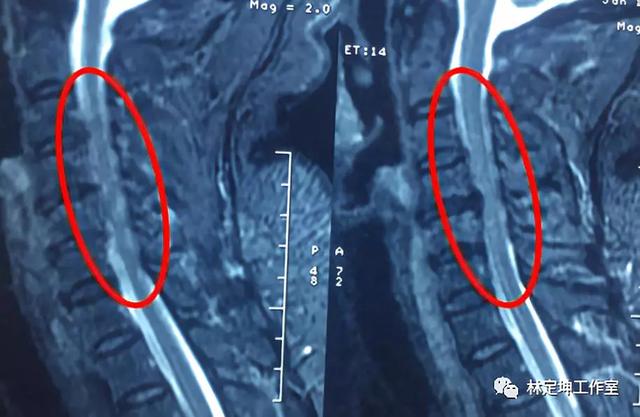

脊髓病变的概述——默沙东诊疗手册 (医学专业人士版)中的病因学、病理生理学、症状、体征、诊断和预后。 默沙东 诊疗手册 欢迎来到默沙东诊疗手册专业版医讯网站 本网站旨在为医药专业人员提供在线服务,如果您不是医药专业人员,建议您退出网站,登录默沙东中国官方网站了解相关信息。 临床常表现为因脊髓受压所致的亚急性慢性脊髓症状。病因多为骨质增生或椎间盘突出引起严重的椎管狭窄。少数情况下,肿瘤或非肿瘤性占位性病变也可导致脊髓压迫。 mri 可见压迫水平髓内 t2wi 高信号病灶,注射对比剂后无强化。颈椎病及其相关脊髓病变 颈椎病是颈椎骨关节炎导致的椎管狭窄,骨关节炎(骨赘)侵入下段颈髓时可引起颈髓病,有时可累及下颈段神经根(脊髓脊神经根病)。 诊断依靠MRI或CT。 治疗可能涉及非甾体类抗炎药和软颈圈或颈椎椎板切除术。 又见 脊髓病变

脊髓病变症状相关问答 问: 脊髓病变的症状是什么? 答: mri示脊髓病变部位呈条形点片状病灶,t1wi低信号,t2wi高信号,多数有强化。 病变多位于后索,后、侧索同时受累者相对少见,一般无单纯侧索受累。 医疗健康 1个回答 推荐 问: 脊髓病变的症状是是什么? 答: 病灶常自脊髓一侧开始 脊髓病变早期的特征主要分为两方面: 1、感觉症状,最突出的疼痛、麻木或者感觉减退; 2、运动症状,大部分患者表现为肢体的力弱,比如一侧或者双侧肢体力量的下降。后期可以出现肢体肌肉萎缩,甚至夏科氏关节等很多其它症状。 所以对于脊髓病变要高度关注肢体,特别是四肢的感觉减退 神经病学 脊髓病变 第14章 脊髓疾病 Diseases of the Spinal Cord 神经病学 (第 6 版) f第一节 概述 f脊髓解剖 1 外部结构 脊髓在C1水平与延髓相连, L1下缘形成脊髓圆锥 脊髓发出31对脊神经 颈 神经8对, 胸 (T)神经12, 腰 (L)神经5, 骶

脊髓病的核磁成像特点

火眼金睛 快速定位诊断颈椎与脊髓病变 Medsci Cn